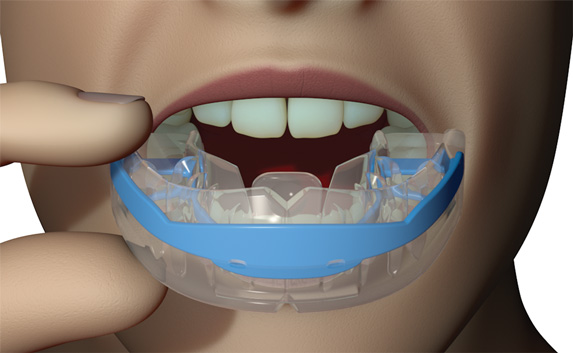

myobrace Medium Myobrace Orthodontic Teeth Trainer Appliance T1, Medium andの詳細情報

Myobrace Orthodontic Teeth Trainer Appliance T1, Medium and。S1。T3。子どもが使用しました。寝るときだけでも効果はあります。お試ししたい方へ。。T3。ポンちゃんです(他の方は購入出来ません)。SE11L ハンドピース OSADA オサダ